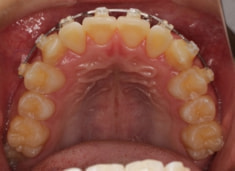

治療前